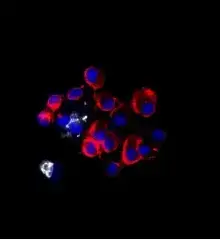

Example images from patient blood samples

Cluster of mesenchymal CTCs - breast

Examples of Portrait+ CTC staining kit samples